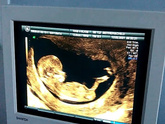

УЗИ. Первый скрининг. Себе в ленту.

13.02.2021г. Акушерский срок 13нед. 1день. Срок по УЗИ 12нед. 2дня. Предпологаемоя дата родов по УЗИ 26.08.21г. КТР 57.7 мм, ЧСС 160, шейка матки 32 мм. На УЗИ сказали девочка будет. Она спала, еле рассшевелила её, … Читать далее